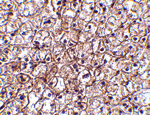

Immunohistochemistry of IFN-b in human liver tissue with IFN-b antibody at 5 ug/mL.